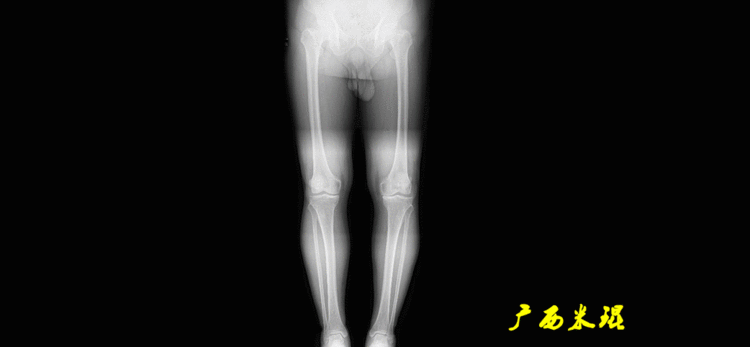

(2)机械轴机械轴是连接近端和远端关节中心点的直线。

机械轴要分前后位及侧位,站立前后位(也就是冠状面)股骨头中心与踝关节中心的连线通过膝关节中心,这是下肢的机械轴线,也就是下肢力线,常说Mikulicz线。冠状面的力线评估在临床工作中最常用、最基础、最重要。

站立侧位(矢状面)股骨头中心与踝关节中心的连线也通过膝关节中心,这也是下肢的机械轴线,这也是下肢力线。

矢状面的下肢力线常常被医生忽视,其实它的改变也是膝关节疼痛的常见原因。

(3)垂直轴也就是下肢的负重轴,它是身体的纵轴线,与地面垂直,由于双髋比双踝的距离宽,所以垂直轴与下肢力线(机械轴)存在3°的外翻。

开始接触时可能我们对这些轴有点混乱,通过下面的这张图片就能清楚的了解下肢几个轴之间的关系。